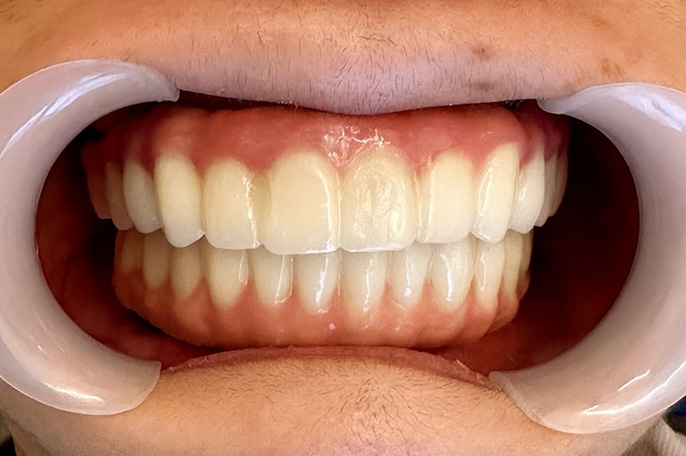

オールオン4 症例・56歳男性主訴:上下の主訴:歯がボロボロで食事ができない。

口の中がボロボロで噛めなくて困っている患者さんです。上下ともにオールオン4治療で、上下4本ずつインプラントを入れて即日で仮歯まで装着しました。

| 治療期間 | 6ヶ月 |

|---|---|

| 治療費 | 5,000,000円(税込) ※施術代、インプラント、被せ物、CT全て込み |

| メリット | 即日で抜歯して仮歯まで入るので一気に改善することが可能です。従来の治療だと1年以上かかるところを6ヶ月程度の治療期間で終えることが出来ました。 |

| デメリット | 外科処置を伴います。 |

| 起こりうる症状 | 外科処置後に腫れ、痛みが出ることがあります。セラミックが破損する可能性があります。 |

術前

術後